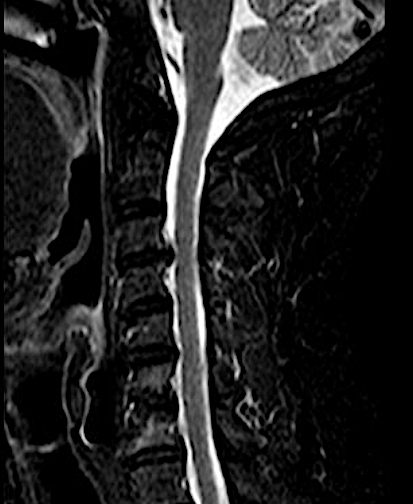

RM cervical 6 meses

Las RX dinámicas demuestran fijación intersomática sin puentes óseos todavía. Obsérvese la recuperación del espacio intersomático respecto al preoperatorio, (indicativo de estabilidad de la artrodesis). El paciente, a los 6 meses de la cirugía, refiere crisis frecuentes de cervicalgias mecánicas altas bien controladas con analgesia de primer nivel y reposo relativo (ha dejado mórficos) y resolución de la braquialgia izquierda.